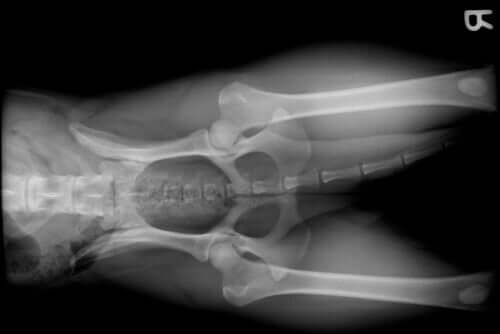

One of the many reasons why a dog visits the veterinarian is the appearance of joint ailments. A dog’s owner usually notices this problem in their dog due to the appearance of lameness and, sometimes, acute pain.

Joint problems in a dog can appear for many reasons, such as:

- The breed. Certain dog breeds, such as the German Shepherd, usually develop hip dysplasia. On the other hand, breeds such as the Golden Retriever, Rottweiler or Doberman, due to their large size and rapid growth, tend to suffer from shoulder or elbow dysplasia.

- Advanced age. Like other mammals, including humans, when dogs get into their old age, conditions linked to this vital stage appear. We’re talking here about canine degenerative joint disease.

- Growth problems. The period of a dog’s growth is a vital moment, as in other species. Therefore, food deficiencies, hormonal problems, or breed can cause joint damage.

- Fractures that involve a joint.

- Anterior cruciate ligament injury. Due to overexertion, excessive exercise, or a small breed type, the anterior cruciate ligament may rupture. This will result in serious joint problems.

- Obesity. In addition to greatly reducing your pet’s quality of life, obesity causes, among other things, joint overload. This can cause serious problems.

- Arthrosis.

- Arthritis.